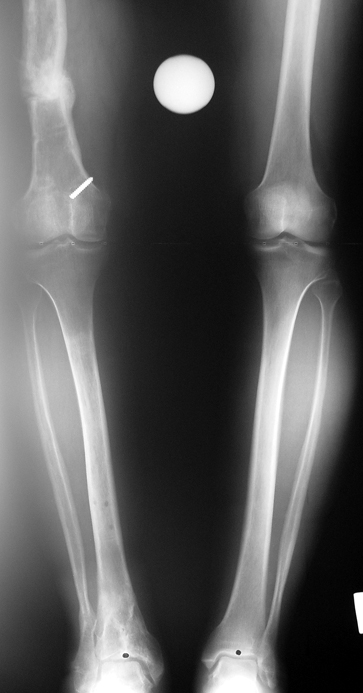

Vaka 1